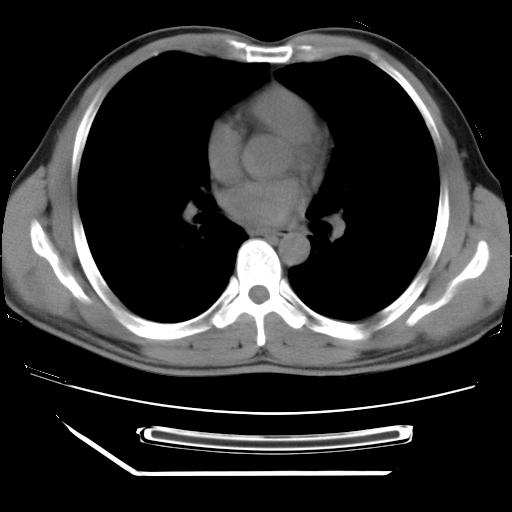

男,38岁,于2009年8月9日晚突发左侧胸痛,今x线提示左下肺阴影,为了明显确诊断,行ct检查,

血常规:嗜酸性细胞增高,单核细胞增高。

病灶发生在下叶,密度均匀,边缘模糊、毛糙,周围血管纹理增强扭曲改变,靠近胸膜处病灶胸膜反应明显。

支持考虑---球形肺炎。

左肺舌叶病变。主体病灶呈类圆形中心密度低,成液化趋势周边班片影分布

考虑肺脓肿

虽然实验室检查支持炎性病变,且病变内有坏死改变(中央呈大片状低密度影),但仍不能掉以轻心,鳞癌也可以有这种影像改变。